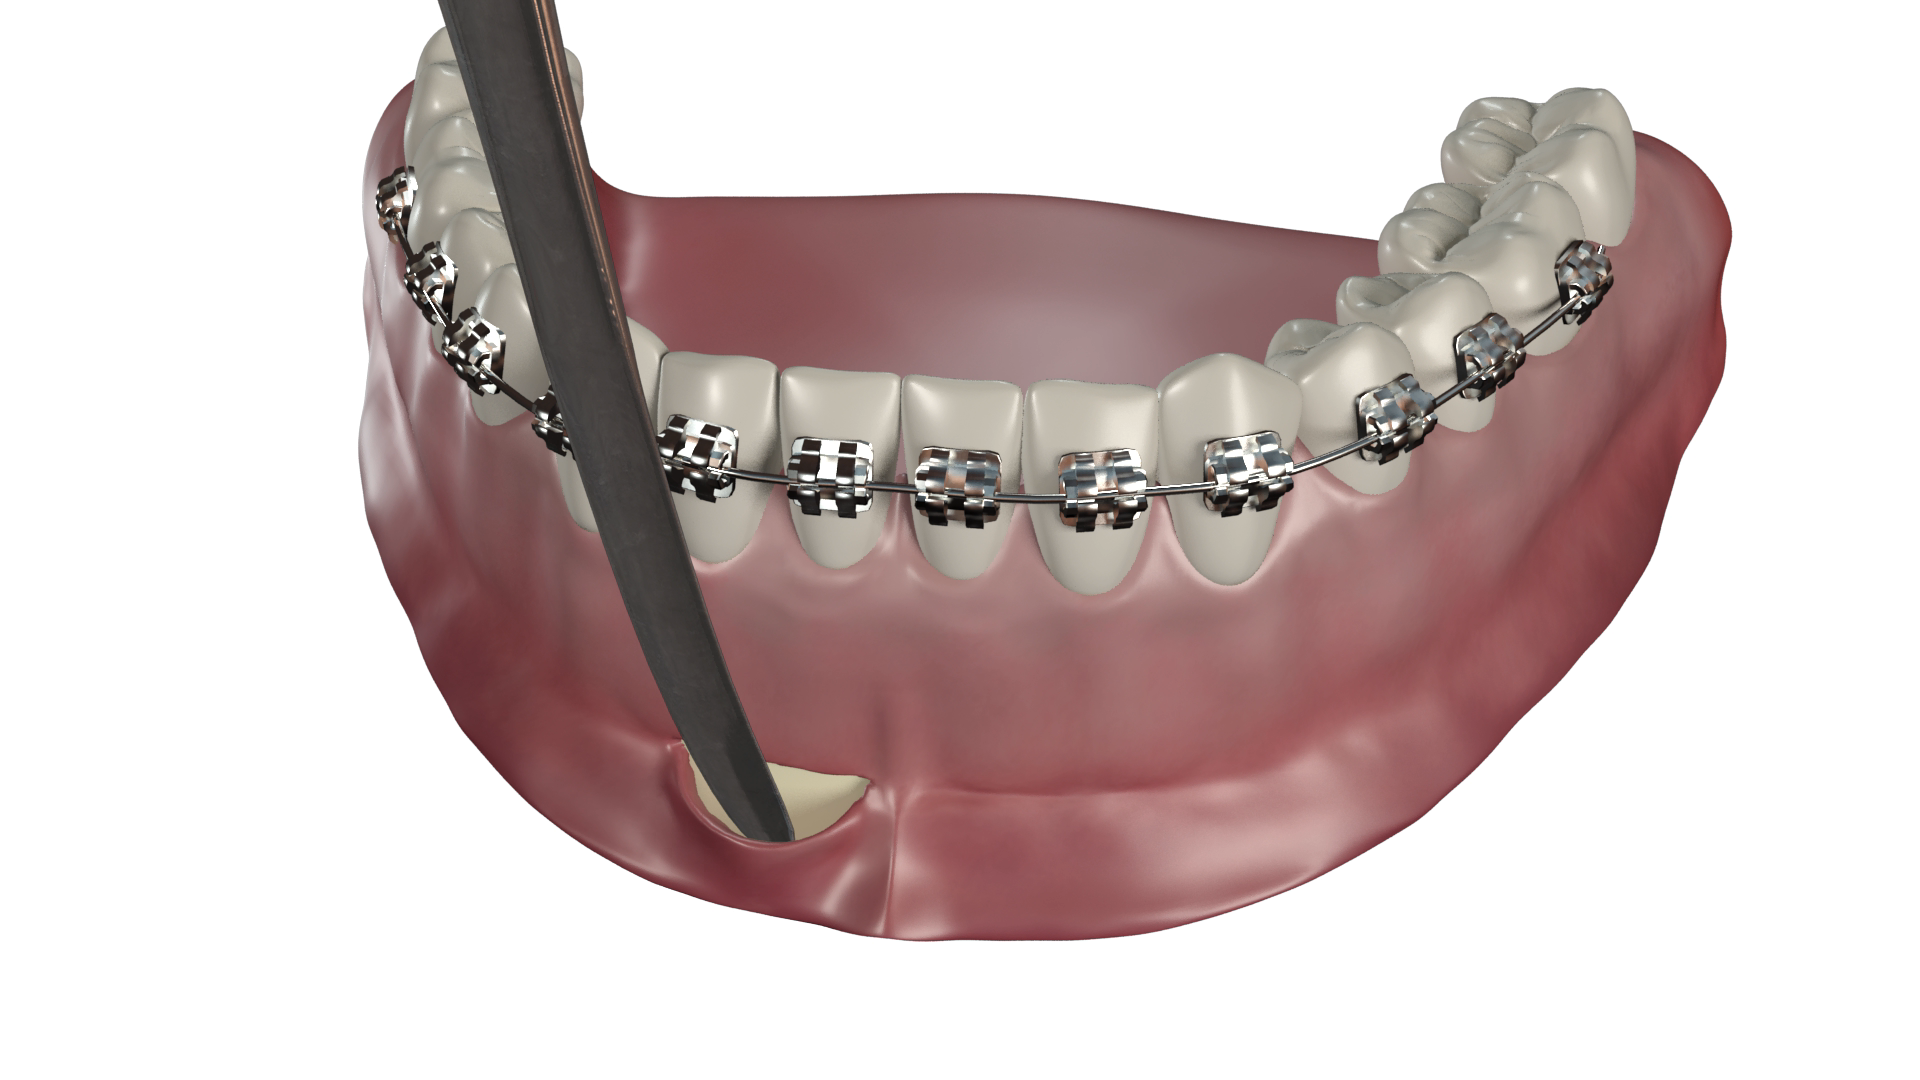

- Mise en forme du fil

Il longe la surface muqueuse sans la comprimer depuis le fond du vestibule, puis est façonné en ressort ou simplement replié en crochet pour pouvoir être relié à l’appareil ou directement aux les dents à déplacer.